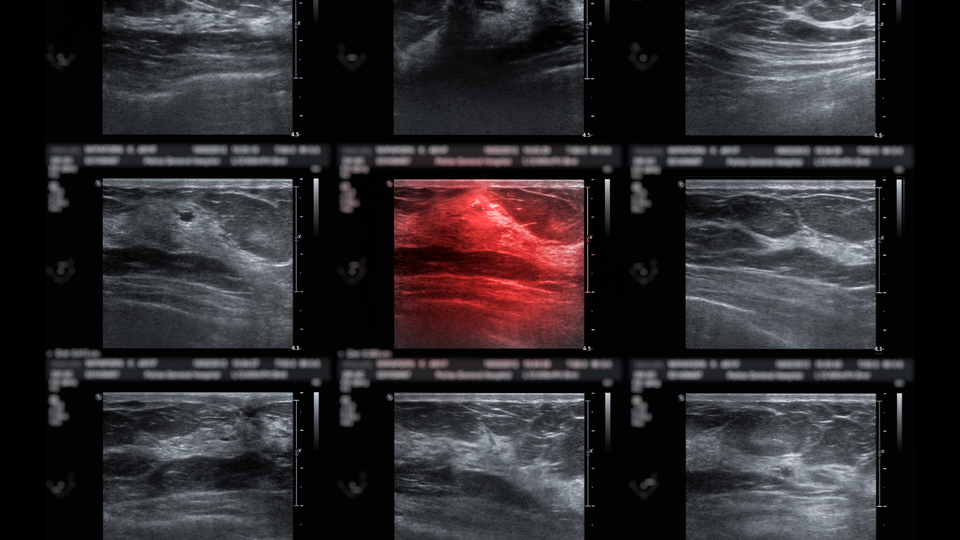

Kadınların tamamen sağlıklıyken, hiçbir şikayetleri yokken gerekli tarama testlerini yaptırmaları gerektiğinin altını çizen Prof. Dr. Vardar, ülkemizde de yaklaşık 10 yıldır Sağlık Bakanlığı tarafından bir tarama stratejisi olduğunu ve bunun KETEM merkezlerinde ücretsiz olarak yapıldığını söyledi. Bu taramalar sırasında meme taramalarının da mutlaka yapılması gerektiğinin altını çizen Vardar, meme kanserinin adeta bir salgın haline geldiğini vurgulayarak "Meme kanseri artık çok genç yaşlarda görülebilen, neredeyse bir salgın diyebileceğimiz hale geldi. Bütün dünyada meme kanseri hastalarının sayısı çok fazla arttı. Bunun çeşitli nedenleri olabilir ama tam olarak nedeni bilinmeyen bir hastalık. Meme kanserinde de mamografi, meme ultrasonografisi ve meme MR'ı dediğimiz tetkiklerle 40 yaş üzeri özellikle 50 yaş üzerindeki kadınların kesinlikle düzenli olarak bu taramaları yaptırmalarını öneriyoruz. Onun dışında tedavi için bizler elimizden geleni yapıyoruz" dedi.